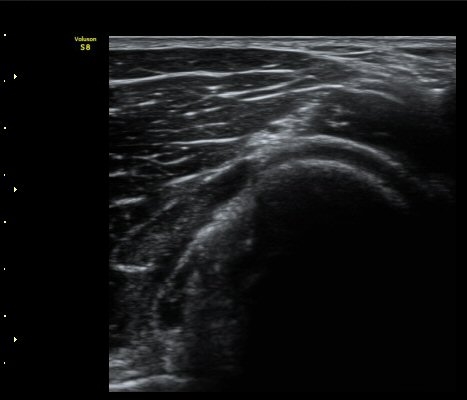

ŽÃËÀÚ¸¦ Á» ´õ ¸»´ÜÀ¸·Î À̵¿ÇÏ´Ï ³¶Á¾Àº ´õ Å©°Ô °üÂûµÈ´Ù(±×¸² 3, 4).